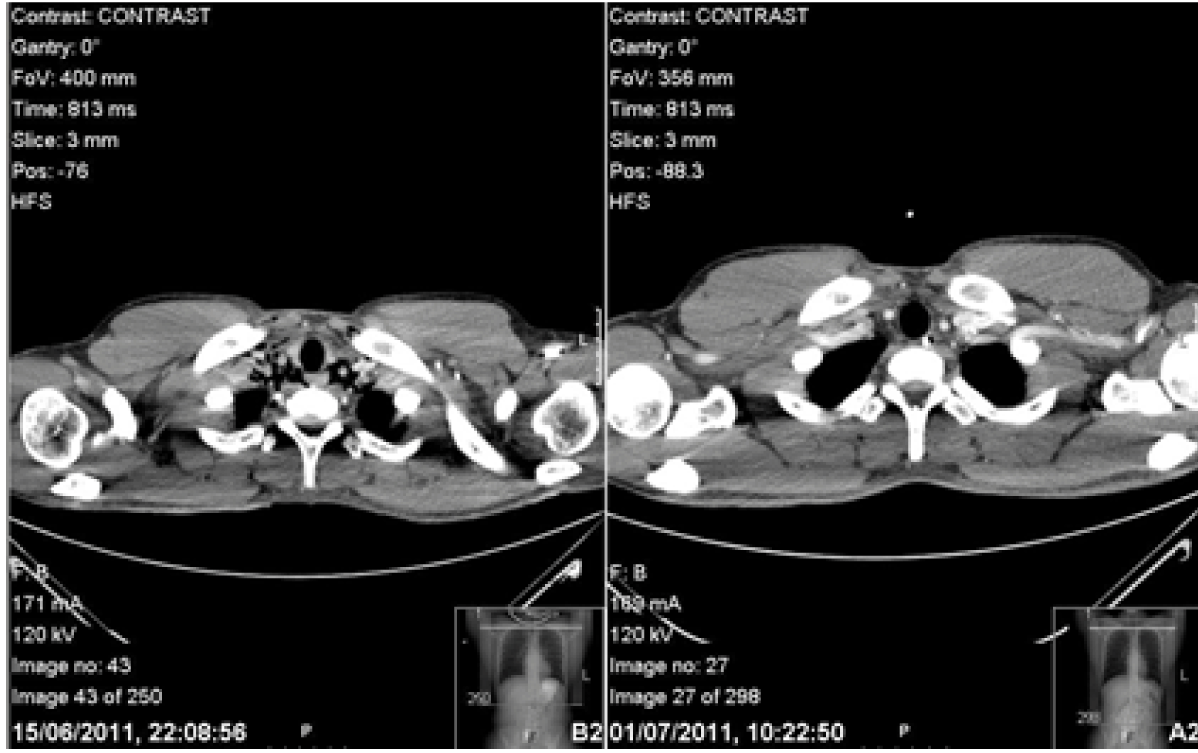

The patient’s symptoms returned spontaneously two days post discharge on the eve of his surgical finals. Subcutaneous emphysema was found on examination. Observations, blood tests and arterial blood gas (ABG) showed no abnormality. Computed tomography scan of chest with IV contrast and Gastrografin swallow showed pneumomediastinum but no leak of Gastrografin. (Figure 2) (Figure 3) Furthermore, there was the dilemma of whether he would be able to sit his exam which was at the same tertiary centre. He was given a stat bag of intravenous fluids, the aforementioned intravenous antibiotics, kept nil by mouth and allowed home to rest. He was admitted directly after his surgical finals and treated conservatively. Nutritional support was given via a nasogastric tube which was inserted under radiological guidance. The patient’s symptoms improved and a Gastrografin swallow study on day-10 was normal. Soft diet was commenced which he tolerated. The patient’s second hospital stay was 12 days. He continued with a fork mashable soft diet until his three month follow-up, which was satisfactory, returning to a normal diet thereafter. Thankfully, the patient passed his finals and continues to work as a doctor. (Figure 4) (Figure 5)

Figure 2: Computed tomography scan of chest with Gastrografin contrast on second admission illustrating a pneumomediastinum with no leak of contrast.

Figure 3: Computed tomography scan of chest with Gastrografin contrast on second admission illustrating surgical emphysema in the neck with no leak of contrast.